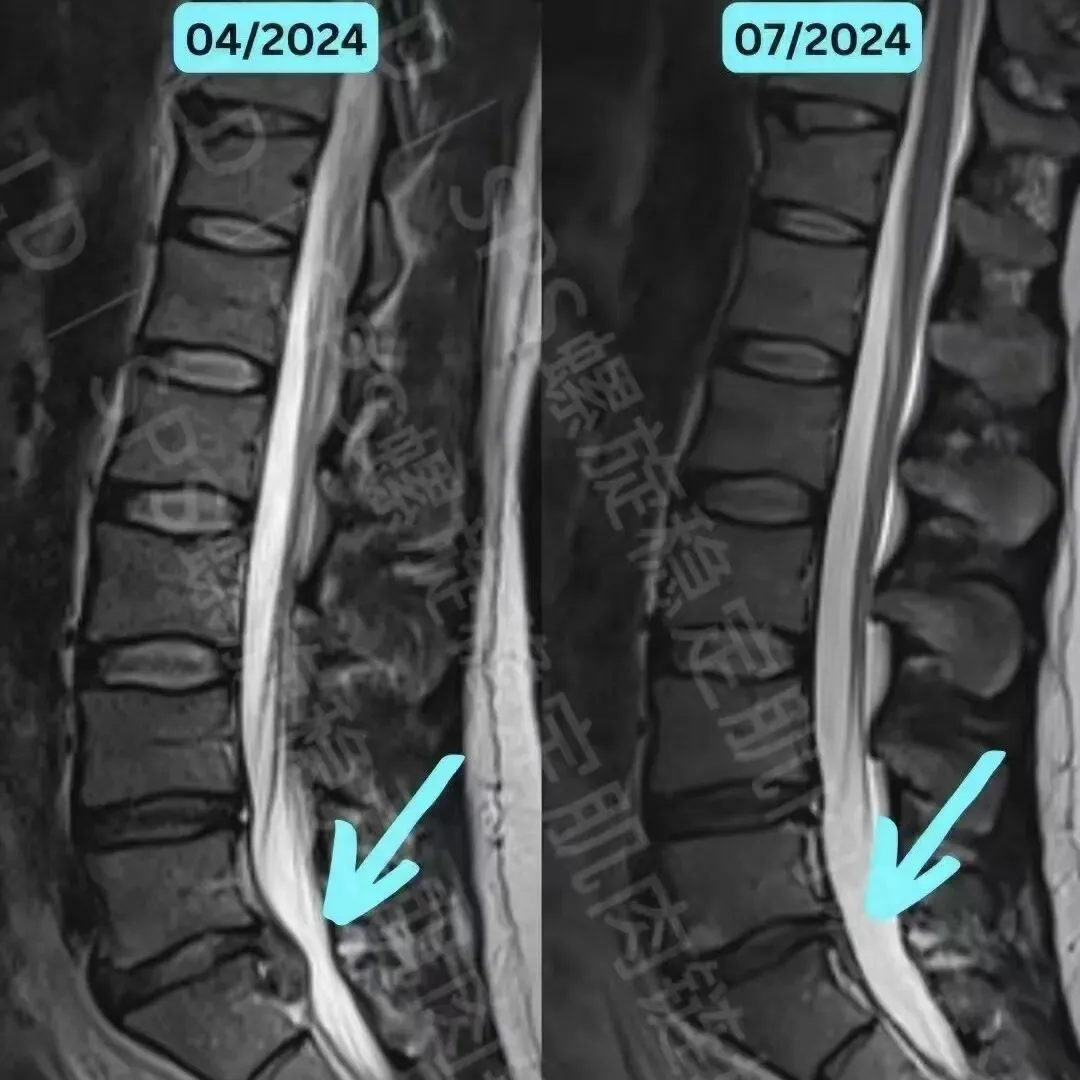

成年人突出改善案例

经过3个月的SPS螺旋稳定肌肉链训练

该患者吸收了L5/S1 椎间盘突出物,身体疼痛感有所改善。